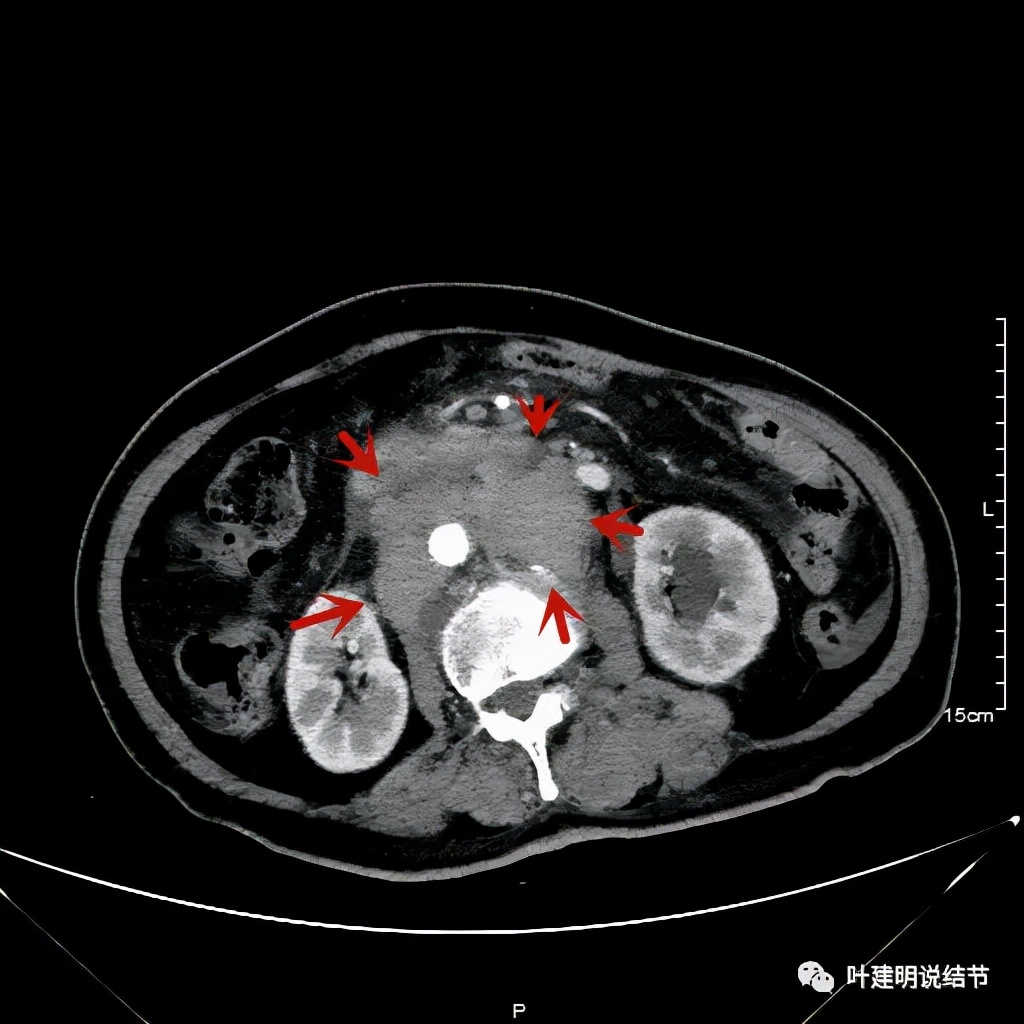

上图同样左侧是治疗前的,右侧经过2周期免疫加化疗后复查的,可见病灶缩小甚至超过9成。下面是治疗前与后来于6月底复查的:

可见经过4个多月的治疗,转移灶已经几乎看不出来了!目前患者无任何不适,正常进食,也无腹部症状或体征,仍在持续特瑞普利单抗维持治疗中。我们期待其更长久的获益与持久的疗效,为其他晚期食管癌积累自己的实战经验(开会或文献上别人的介绍没有自己遇到的如此直观,也没有如此深的印象。所以我一直觉得临床经验,尤其自己亲身经历积累的经验才更有说服力,也更有感受)。